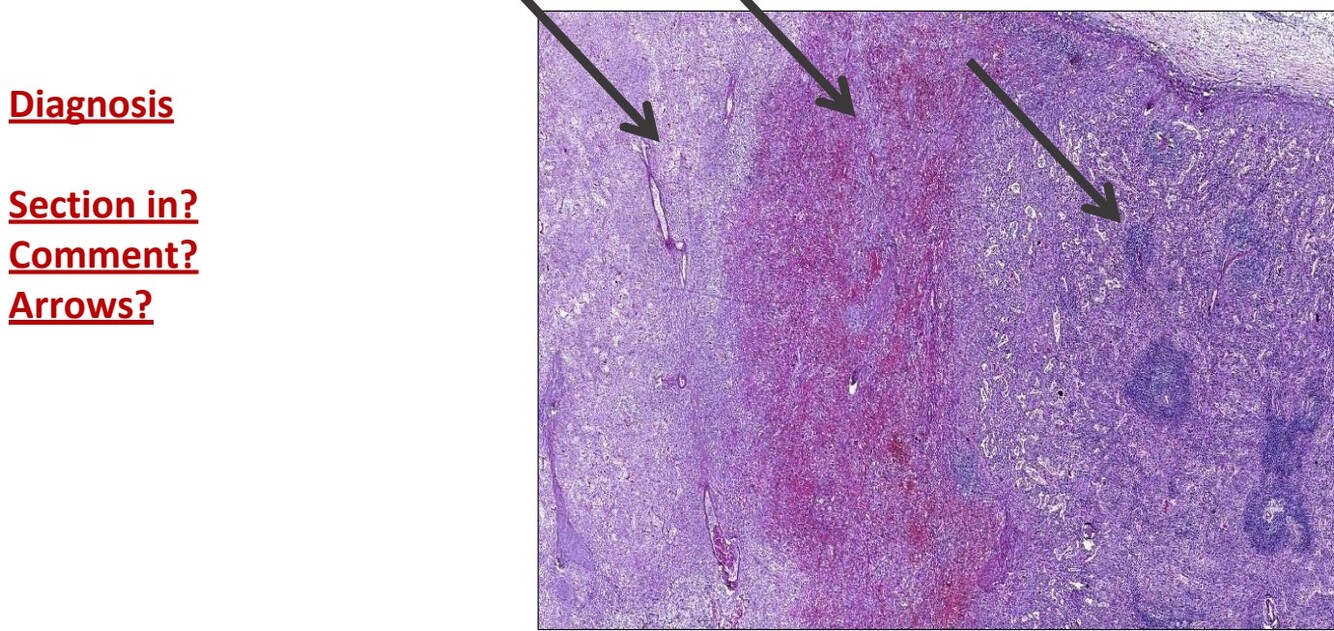

Caseating TB

In lymphnode

Lymph node is enlarged and partially effaced

Multiple tubercles are seen around caseation

Black arrow is Langerhans giant cell

Red arrow is caseation